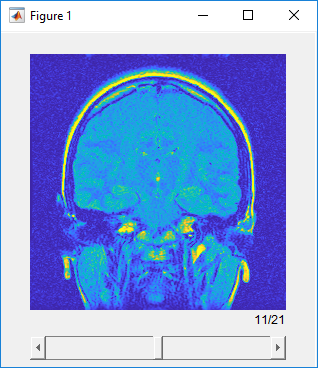

Используйте sliceViewer смотреть на отдельные срезы в объемах. Когда средство просмотра открывается, оно отображает среднее изображение в стеке в направлении, заданном SliceDirection свойство. Используйте ползунок, чтобы перейти через объем и просмотреть отдельные срезы.

sliceViewer( отображает шкалу полутонов или объем RGB S)S в фигуре. Фигура включает ползунок, который можно использовать, чтобы просмотреть отдельные срезы объема.